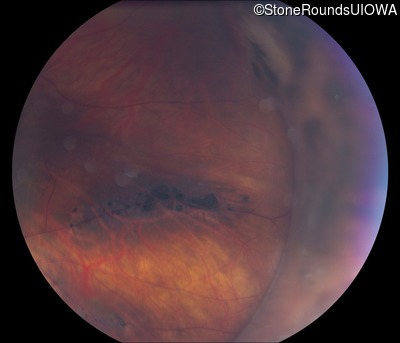

Visit at age: 36 years

Fundus Photography - Right - 20/40 +2

Exemplar